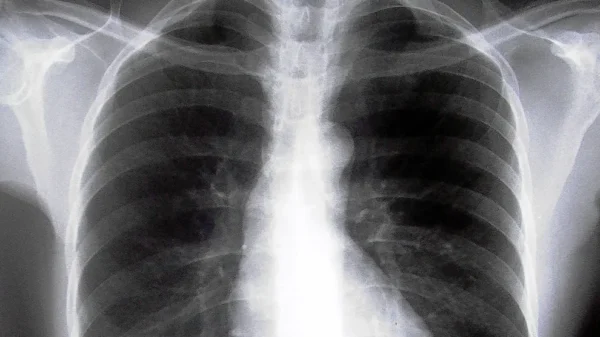

La enfermedad pulmonar obstructiva crónica (EPOC) es una patología respiratoria crónica y progresiva caracterizada por una obstrucción persistente del flujo de aire en los pulmones. Al inspeccionar el tórax de un paciente con EPOC, se pueden identificar dos manifestaciones físicas distintivas: hiperinflación y disminución del desplazamiento diafragmático.

La hiperinflación pulmonar, resultado directo de la obstrucción crónica de las vías respiratorias, se manifiesta visualmente por un aumento en el diámetro anteroposterior del tórax. Este fenómeno provoca una apariencia más amplia y redondeada del tórax, conocida coloquialmente como «tórax en tonel». La acumulación de aire atrapado en los alvéolos pulmonares durante la exhalación incompleta contribuye a esta hiperinflación. Además, durante la inspiración, se puede observar un descenso limitado de las costillas inferiores, lo que se denomina «accesorios inspiratorios». Esta limitación de la expansión torácica puede resultar en una disminución de los espacios intercostales apreciable en la inspección.

Por otro lado, la disminución del desplazamiento diafragmático es otra característica prominente en la inspección del tórax en pacientes con EPOC. El diafragma, principal músculo involucrado en la respiración, puede ver comprometida su capacidad para contraerse y expandirse completamente debido a diversos factores asociados con la EPOC, como la pérdida de elasticidad pulmonar y la debilidad muscular. Esta disminución en la movilidad diafragmática se traduce en una respiración más superficial y menos eficiente, exacerbando la sensación de disnea experimentada por los pacientes con EPOC.